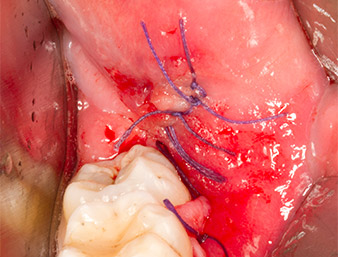

Puis le tissu osseux autogène (Fig. 13) est placé dans l’alvéole et le défaut osseux voisin (Fig. 14). Une membrane de collagène recouvre les fragments osseux à hauteur de l’os afin de protéger le nerf exposé (Fig. 15). Pour refermer le tissu mou ouvert, on utilise du fil de suture Vicryl, USP 4.0 (Fig. 16). Une préparation à base d’ibuprofène (Seractil 400 mg, 3x1) et un antibiotique associant amoxicilline et acide clavulanique (Augmentin 1 g, 2x1) sont prescrits en postopératoire.

La plaie cicatrise sans complications (Fig. 17) et les fils sont enlevés au bout de sept jours. Le patient retrouve une sensibilité normale. Les douleurs ont cessé.